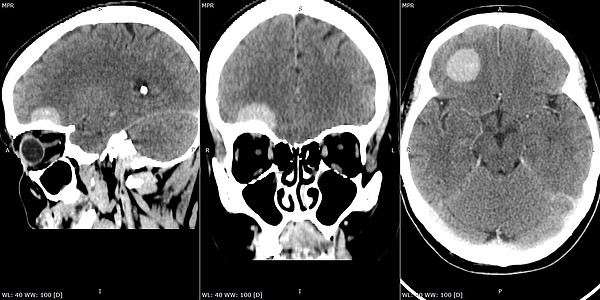

В Кировской областной клинической больнице активно развивается малоинвазивная нейрохирургия